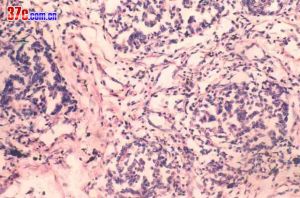

鏡下:實性包塊,肺之基本結構消失,在包塊的邊緣部分見病變向鄰近的肺實質的間質擴展,使有些肺泡或細支氣管散在其中;肺泡上皮增生明顯,肺泡間隔內由成團成片的來源不明的腫瘤細胞占據,瘤細胞可有異型性、分裂像。間質可見增生、透明性變,其中的腫瘤細胞表現呈“浸潤性”生長。

肺炎性假瘤病因尚不十分清楚,多數學者認為系細菌病毒感染後非特異性炎症的機化、修復而引起的局限性瘤樣慢性增生性病變,形成的腫塊壓迫周圍肺組織或周圍肺組織反應性改變,形成假性包膜,所以一般邊界光整。少數包膜不完整、無包膜或有胸膜粘連者,邊緣可不光整。在病理上依其主要的細胞成分分為組織細胞瘤型、硬化性血管瘤型、漿細胞肉芽腫型、細胞上皮乳頭樣增生型和假性淋巴瘤五個類型。根據影像學表現可分為浸潤型和腫塊型,但病理上分類與影像學改變沒有必然的聯繫。